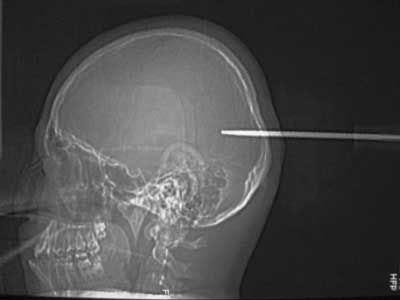

1. Người không may mắn này đã bị phần đầu của chiếc tuốc-nơ-vít đâm thẳng vào sau đầu. Tin hay không tin là tùy bạn nhưng các bác sĩ đã lấy được vật này ra và bệnh nhân đã phục hồi hoàn toàn: